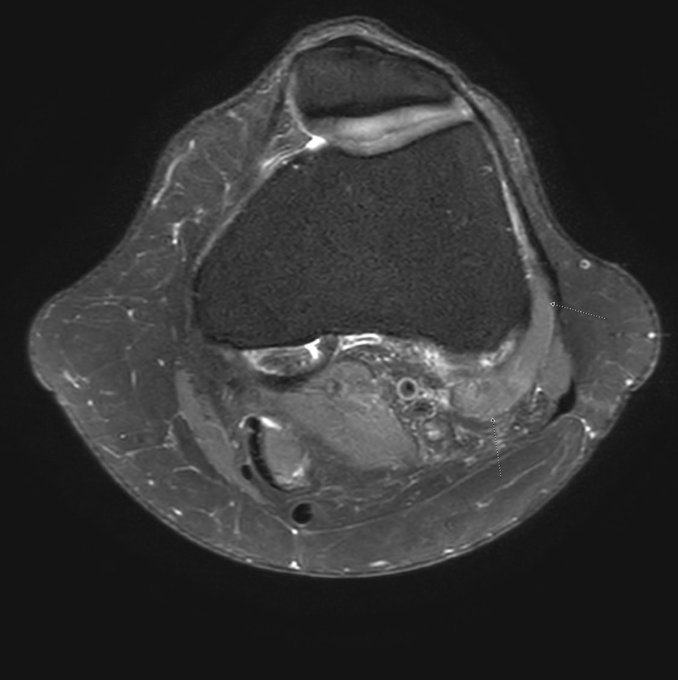

Bilateral muscular mass lateral to the distal metaphyseal femur. Anomalous Origin of the Lateral Head of the Gastrocnemius Muscles. https://t.co/0JXiVsObdq #MSKrad #knee #radiology #orthotwitter #FOAMrad #radres